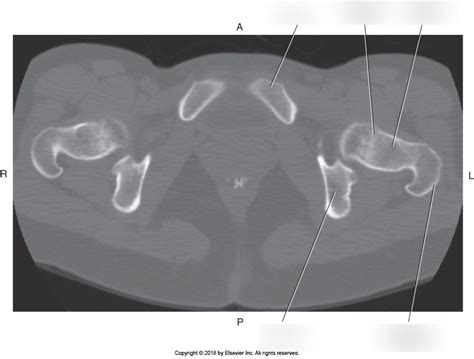

When we talk about the axial pelvis , we’re primarily referring to the pelvic girdle , which is made up of three main bones: the ilium , the ischium , and the pubis . These bones fuse together during adolescence to form the innominate bones , with each side of the pelvis having one. These innominate bones then join together at the front via the pubic symphysis and at the back with the sacrum , which is part of the vertebral column. This bony structure forms a ring that’s incredibly strong and stable, yet flexible enough to allow for movement. The ilium is the largest bone, forming the upper, flared part you can feel at your hips. It has a prominent crest, the iliac crest , which is a landmark for many medical procedures. Below the ilium, you have the ischium , which is the part you sit on – yep, that’s your “sitting bone”! Finally, the pubis forms the front and lower part of the pelvis, meeting its counterpart from the other side at the pubic symphysis. Together, these bones create the acetabulum , a deep socket that articulates with the head of the femur (thigh bone) to form the hip joint. This joint is a marvel of engineering, allowing for a wide range of motion while supporting your body weight. The intricate architecture of the axial pelvis, with its curves and articulations, is designed for maximum strength and efficient load transfer from the trunk to the lower extremities. It’s a testament to nature’s design, ensuring we can stand tall and move with grace. The way these bones are shaped and connected is key to its stability, preventing excessive movement that could lead to injury. The pelvis also plays a vital role in protecting internal organs, forming a protective basin for the bladder, reproductive organs, and lower parts of the digestive tract. So, while it’s a strong structural component, it’s also a vital protective cage for some of our most sensitive organs. The robustness of this bony framework is essential for countless activities, from the simple act of standing to the complex demands of athletic performance. Its deep sockets and strong ligaments ensure that the hip joints remain stable, even under significant stress.